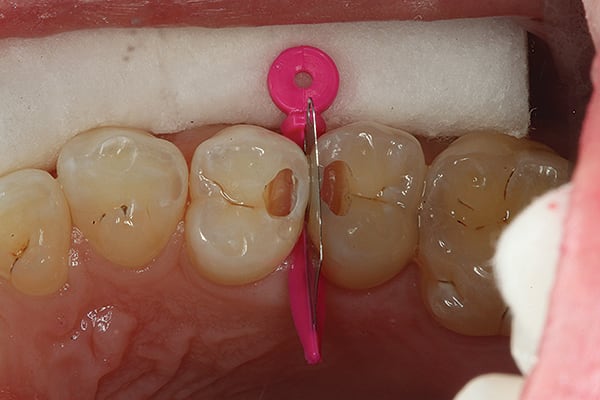

3. The tunnel preparations have now been completed. Note the affected dentin present but no decay.